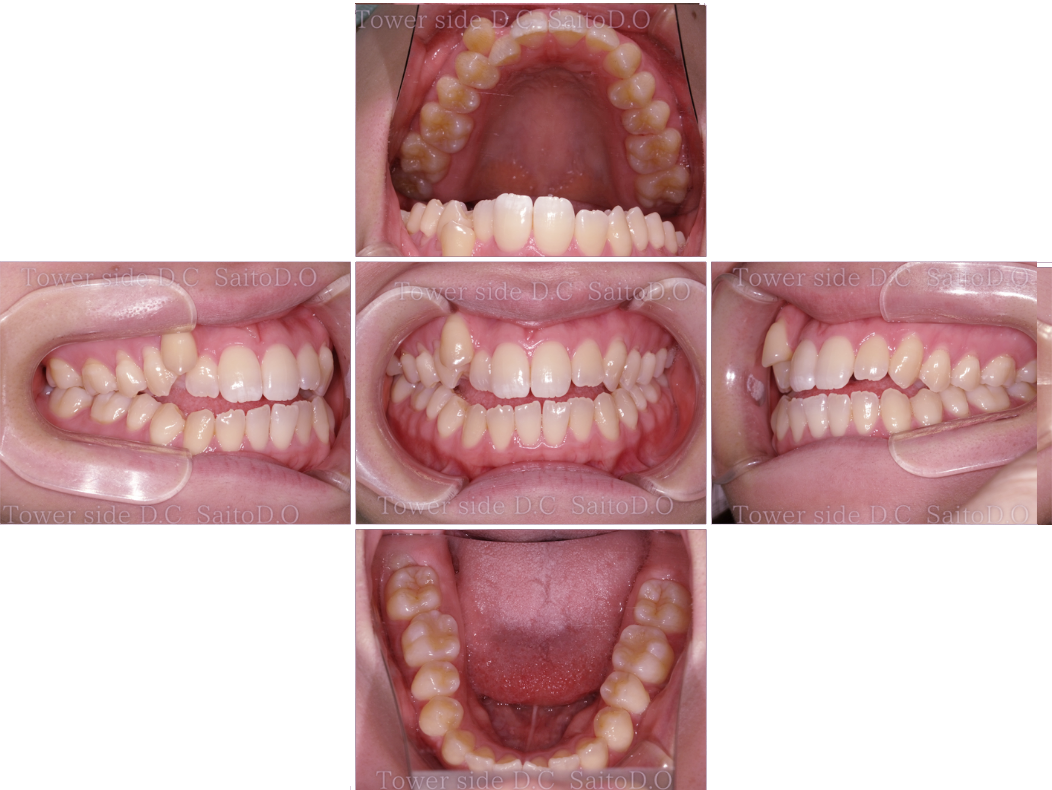

症例(施術前)

症例(施術後)

主訴 前歯が噛み合わない

状況

• 開咬

• 舌癖

• 八重歯

• 叢生

• 正中ズレ

治療費 968,000円(税込)(自由診療)

治療期間 1年2ヶ月

治療内容 第一小臼歯を4本抜歯。マウスピース矯正を主軸として行い、挺出用フックや左下567はワイヤー併用し、咬合改善を行なった。その後、保定装置(リテーナー)を使用し安定している。